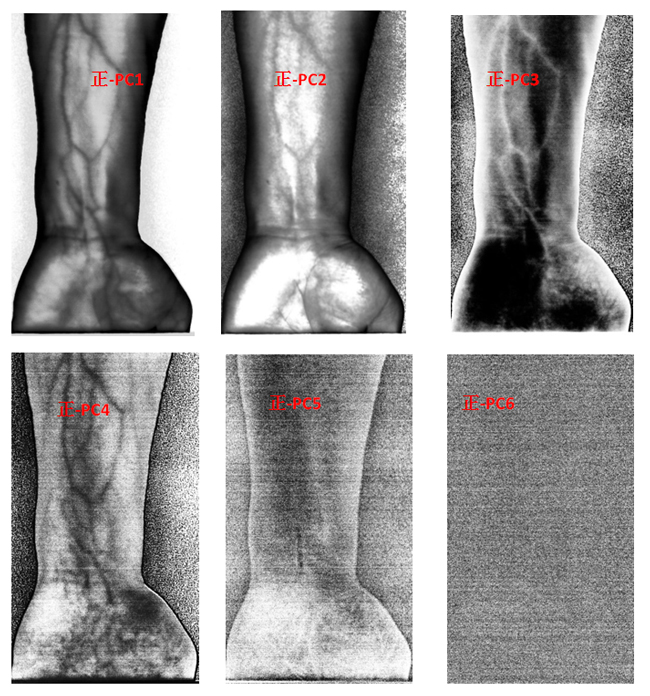

為了客觀地識別手臂上的靜脈,對經(jīng)預(yù)處理后的高光譜數(shù)據(jù)進(jìn)行主成分分析(Principal Component Analysis, PCA),去除波段之間的多余信息、將多波段的圖像信息壓縮到比原波段更有效的少數(shù)幾個轉(zhuǎn)換波段下。圖9為手臂正反面經(jīng)PCA變換后的前6個主成分。

圖9 手臂正反兩面PCA處理后的前6個主成分